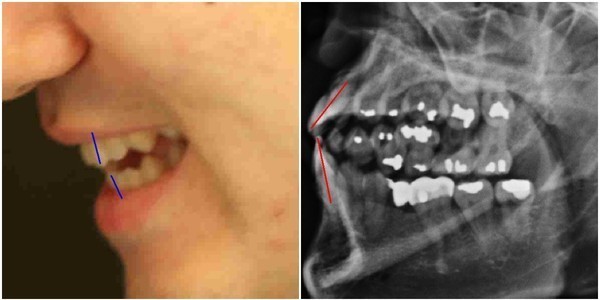

재판부가 건강보험심사평가원장으로 재임 중인 손명세 교수를 증인으로 채택한 이유를 이해하기 위해서는, 이 사건의 숨겨진 쟁점 중 하나인 ‘박주신씨 구외 엑스레이(이하 치아 엑스레이)에서 나타나는 의혹’을 알아야 한다.

박주신씨의 치과진료기록은 풀리지 않는 미스터리로 남아있다.

- ▲ ▲ 박주신씨의 치아 상태를 알수 있는 엑스레이 사진 자료. ⓒ 뉴데일리DB

- ▲ ▲ 박주신 엑스레이(X-RAY)에 대한 치의학 박사의 분석자료. ⓒ 뉴데일리DB

양승오 박사 등에 대한 검찰의 수사가 진행되던 지난해, 이 사건 피고인들은 박주신씨 치아 X-Ray를 근거로, 박주신씨의 신체를 촬영했다는 X-Ray 속 피사체가 제3의 인물일 가능성을 주장했다.

주신씨의 치아 X-Ray는 허리 MRI 촬영 과정에서 찍힌 X-Ray 사진들 중에서 치아가 보이는 X-Ray 사진이다.

따라서 치아 X-Ray 상에 나타나는 각종 의혹은, 허리 MRI와 더불어 해당 피사체가 주신씨가 아닐 가능성에 무게를 더한다.

피고인들이 치아 X-Ray를 근거로, '피사체 바꿔치기' 의혹을 강하게 제기한 이유는, X-Ray에 나타난 치아의 상태가, 도저히 20대 중반 청년의 것이라고는 보기 힘든 특징을 갖고 있었기 때문이다.

주신씨 치아 X-Ray 사진을 보면, 치아 상태가 매우 불량하다는 사실을 알 수 있다. 치아 2개는 아예 없고, 아말감으로 때운 치아가 무려 14개에 달한다.

수은증기 방출 논란으로 문제가 되고 있는 아말감(Amalgam) 치료는 여러 가지 단점을 갖고 있어 사용빈도가 크게 줄고 있다는 것이 치과의료계의 공통된 평가다.

서울 방배동에 사는 중산층 청년이, 치과의사는 물론 환자들도 기피하는 아말감을 이용한 치과 치료를 이처럼 많이 받았다는 것은, 쉽게 받아들이기 어렵다는 것이 이들의 지적이다.

더욱 의심이 가는 부분은 주신씨의 경우, 하악 좌측 1소구치(아래쪽 좌측 첫 번째 작은 어금니)까지 아말감으로 치료했다는 사실이다.

이런 경우는 매우 드물다는 것이 치과의사들의 일반적인 견해다.

이 사건 피고인 중 한명인 치과의사 김우현씨는, 주신씨의 영구치가 맹출을 시작했을 것으로 추정되는 1990년대 중반 이후, 젊은 사람이 1소구치들을 포함한 구치부 치아 전체를 아말감으로 치료했다고 보기엔 무리가 있다고 지적했다.

치의학 박사 C씨는 뉴데일리와 기자와의 인터뷰에서 “주신씨의 전체적인 치료 상태를 보면, 소위 말하는 '야매'로 했을 가능성이 높다”고 밝혔다.

“(주신씨의 것이라고 알려진 구외 X-Ray 사진을 보면) 최근 국내에서 교육받은 치과의사의 치료라고 생각할 수 없을 정도.”

“(주신씨 구외 X-Ray 사진 상의) 45번, 46번 보철치료 및 치아 상실 문제도 마찬가지다. 보철물로는 상당히 저렴한 비귀금속 합금을 사용한 것으로 보인다. 37번 치아는 아예 없는 상태로 방치하기도 했다.”

“박주신씨의 가정환경을 고려하면, 이런 치료를 받았을 가능성은 1%도 안 된다. 서울 방배동에 거주했던 중산층 이상의 가정에서는 흔치 않은 상황.”

주신씨의 치아 아말감 치료와 관련돼, 김우현씨는 “혹자는 아말감 치료를 10개 이상 한 게 무슨 대수냐? 하면서 무시하는 경향이 있지만, 이는 모든 인과관계와 사실들을 무시하려는 것”이라고 비판했다.주신씨의 치아 X-Ray 사진 상에 나타나는 의문들은, 양승오 박사 등이 주신씨의 병역비리 의혹을 제기하게 된 핵심 요인 중 하나였다.